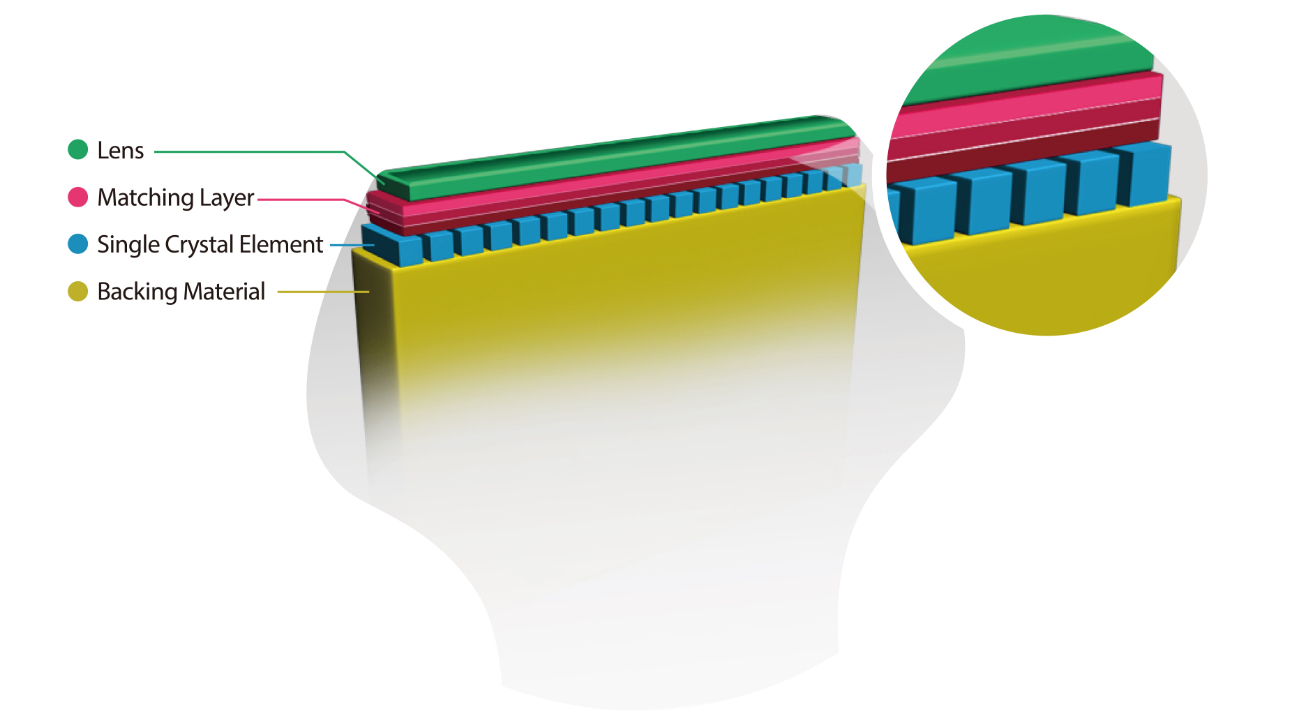

Based on Mindray's new generation ultrasound platform, mQuadro, M9 has raised the industry standards to an all new level. Advanced signal transmission and reception processors provide highly sensitive and accurate echo detection. Innovative transducer technologies allow for better penetration, higher resolution, greatly enhancing your diagnostic experience.